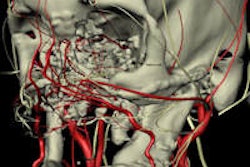

For the current study, the researchers screened a university hospital's imaging database for whole-body trauma CT scans completed between 2006 and 2018, identifying 994 CT scans. Cases of isolated maxillofacial trauma were not included.

A radiologist with seven years of experience reanalyzed the scans for possible dental trauma findings. The images were evaluated using 3D reconstructions, and the radiologist and a consultant radiologist with 17 years of experience reached a consensus on any cases that were unclear.